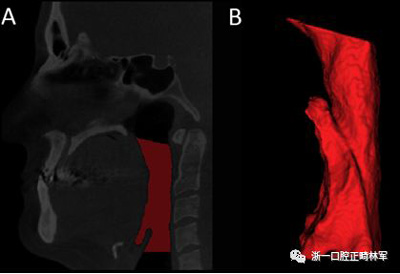

咽腔體積(PS體積)的分析是從三維模型進(jìn)行的。三維模型的重建采用軟件Insight ITK-SNAP(版本2.4.0; Cognitica,Philadelphia,Pa)的半自動分割模式建立,該模型以立方毫米測量結(jié)構(gòu)的體積。本研究中測量的體積對應(yīng)于口咽和下咽部之間的聯(lián)合。為此,我們按照Park等描述的解剖學(xué)定義確定了從后鼻棘到第一頸椎的最低點的上部參考線,以及在垂直于內(nèi)側(cè)矢狀面的第四頸椎最低點上描繪的下部參考線(圖5)。

圖5.A,使用文本中描述的參考點對咽腔進(jìn)行分割(紅色); B,口咽和下咽部之間的聯(lián)合體積。